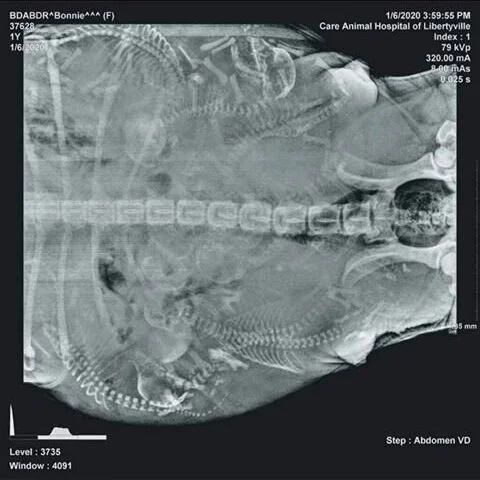

puppy count x ray

Pregnant Miniature Schnauzer X-Ray Puppy Count. Mama had 11 Moyen Goldendooldes but we lost 2 right after birth. Have you ever seen an X-Ray of a pregnant dog.

Just try to count their spines. Fetal count radiographic procedures are commonly performed in veterinary medicine. I was afraid she would only have one one.

Gypsy had her X-Ray for her puppy count today. Ad Earn 2K Treats Points for Every 20 Spent Online. Judys due any day now so we decided to get an x-ray taken to see how many pups she is carrying.

X Ray Of Cavalier King Charles Spaniel 56 Days Pregnant 4 Puppies Seen. When can you get a puppy count X-ray. These studies take place late in an animals pregnancy and allow the veterinarian or veterinary.

X-rays most often give us an exact count of the litter but even with the best images some puppies could be hiding behind another puppy or the dams spine. X-rays most often give us an exact count of the litter but even with the best images some puppies could be hiding behind another puppy or the dams. If the x-rays are performed too early in a dogs pregnancy it will.

Joined Jul 5 2020. Posted by 1 year ago. The best time to perform x-rays for a puppy count is one week prior to the expected due date.

How Many Puppies Can You Count In This X Ray Watchdog Mary